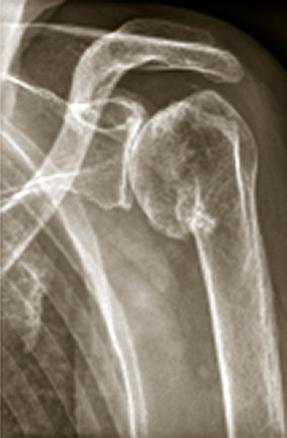

Omarthrose centrée

Radiolographie d'une omarthrose centrée